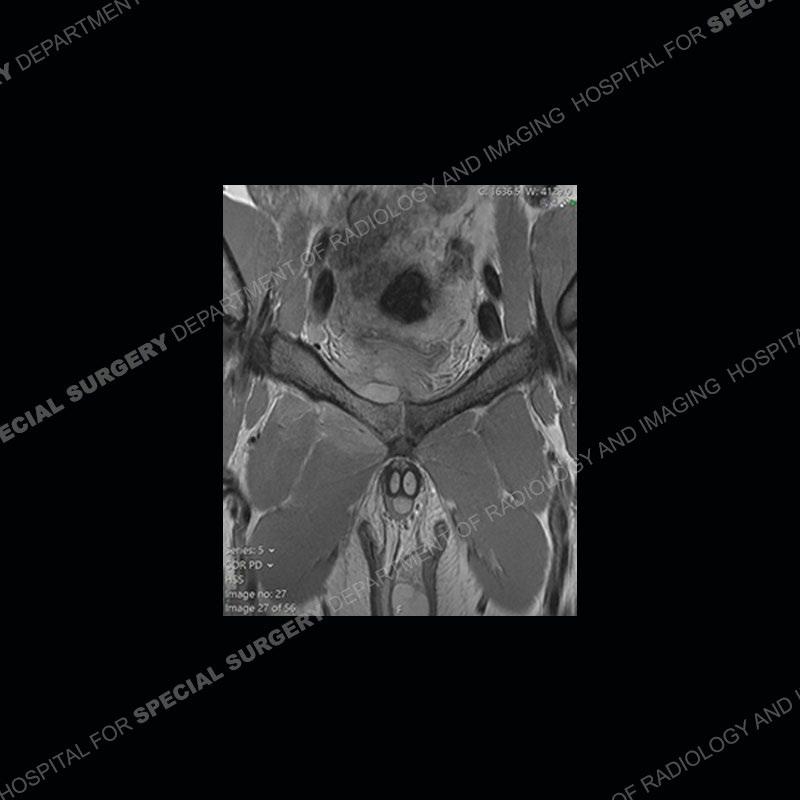

Radiographs did not demonstrate any clear abnormality. The MRI shows markedly abnormal signal of the right superior pubic ramus and abnormal signal/”mass” extending into the adjacent soft tissue. The inferior articular surface of the ramus showed what was thought to be bony destruction. CT examination shows a destructive process of the right superior pubic ramus.

Subsequent MRI in a very short time interval shows markedly increased abnormality of the ramus and increased edema and “mass” of the soft tissue. Post contrast imaging shows multiple, rim enhancing collections of the soft tissue and similar albeit less conspicuous enhancing collection of the ramus.

Diagnosis: Osteomyelitis and Soft Tissue Abscess